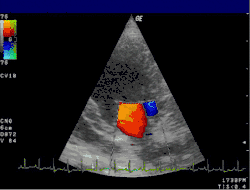

Color doppler

Color doppler is a form of 2D echo in which the doppler shift of the structures is shown as color. Typically, this is shown as red and blue with red indicating movement toward the transducer and blue indicating movement away from the transducer. This can be used to show blood flow through the valves to visually indicate the direction of blood flow. Abnormal blood flow can reflect stenosis and regurgitation of the valve. Color doppler can also show blood flow in abnormal locations such as with septal defects (ASD or VSD).

Color doppler can also be applied to M-mode. Using color doppler in this way gives better visualization of the changes in flow with time due to the higher frame rate with M-mode.